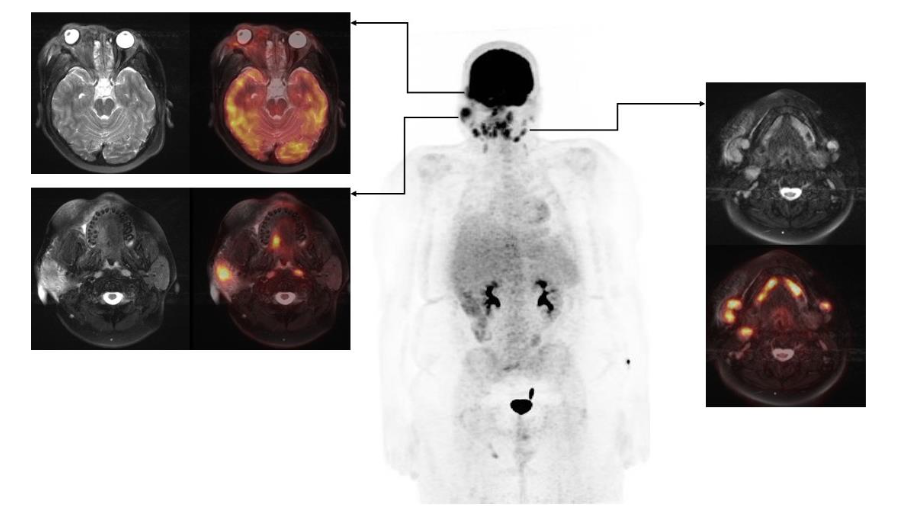

FDG PET/MRI was used to characterize the extent of the disease and determine the optimal site for tissue biopsy. FDG PET/MRI revealed multiple markedly FDG-avid cervical lymph nodes, focal intense uptake in the right parotid region, and focal uptake in the right orbital infiltrative mass with maximum Standardized Uptake Value (SUV) of 13. Guided by FDG PET/MRI, the patient underwent a biopsy of the most FDG-avid region of the right orbital mass, which was diagnosed as necrobiotic xanthogranuloma with increased IgG4 expression. The patient was treated with cyclophosphamide, corticosteroid, and high-dose IVIG followed by bone marrow stem cell transplantation and showed a good response in terms of both imaging and clinical evaluation. The genetic and histopathologic findings of this case are discussed in detail by Guess et al.